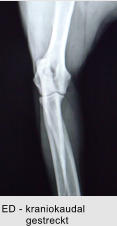

Bartagame - dorsoventral ED - kraniokaudal         gestreckt HD - gestreckt

Röntgen Wir verwenden ein digitales Röntgensystem, dies bietet gleich mehrere Vorteile: Innerhalb von Sekunden ist die Röntgenaufnahme auf dem Monitor sichtbar - lange Wartezeiten, die früher für die Entwicklung notwendig waren, entfallen. Die Aufnahmen können auf Wunsch direkt auf eine CD gebrannt und von Ihnen mitgenommen werden - ein lästiges Hin- und Herschicken entfällt. Im Falle einer notwendigen Überweisung in eine spezialisierte Klinik nehmen Sie die Röntgenaufnahmen für die Kollegin / den Kollegen direkt mit.